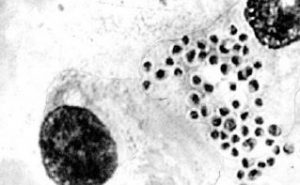

- **Microscopy and Staining:**In the Wright or Giemsa stained specimens, Histoplasma capsulatum is found intracellularly within the cytoplasm of endothelial or mononuclear cells.

H capsulatum yeasts: Small round or oval cells, measuring 2-5 μm in diameter. They require differentiation from the amastigotes ofLeishmania donovaniwhich can also be found in mononuclear cells.